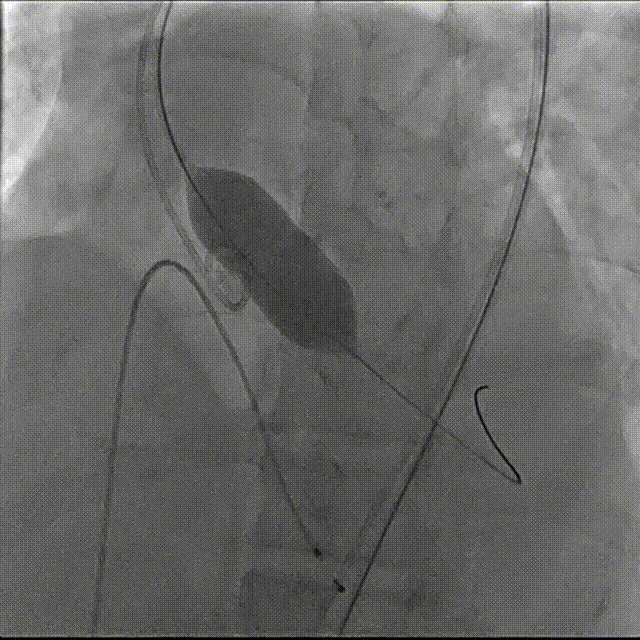

主动脉根部造影

第二次完全释放

最终造影